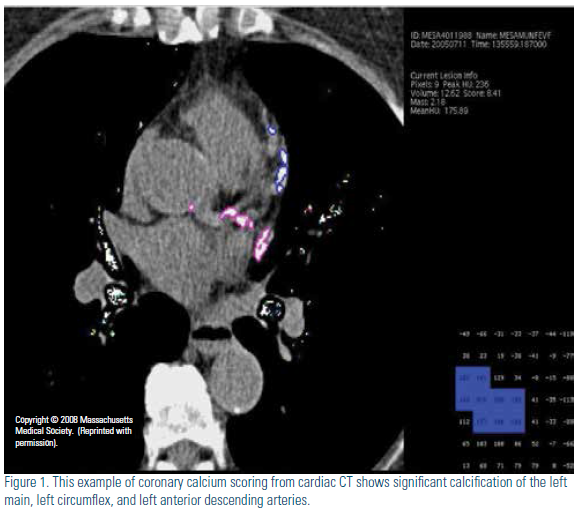

Atherosclerotic cardiovascular disease (ASCVD) is the major cause of morbidity, mortality, and medical costs in the U.S. While ASCVD is largely preventable with a healthy lifestyle and effective medical therapy, identification of individuals at risk for ASCVD events continues to be a challenge. Historically, the Framingham Risk Score (FRS)1 and now, the Pooled Cohort Risk Equation,2 are used to estimate 10-year risk of coronary heart disease (CHD) and ASCVD, respectively, and are incorporated into cholesterol treatment guidelines.3,4 Unfortunately, many patients experiencing ASCVD are not classified as high risk by such approaches.5 The role of biomarkers and imaging tools has been of interest to those trying to improve risk stratification of asymptomatic individuals. One of the most promising such modalities is coronary calcium scanning by computed tomography (CT); the coronary artery calcium score (CACS) (Figure1) estimates subclinical atherosclerotic burden. The theoretical framework for CACS is based on autopsy studies that consistently demonstrate a unique association between calcification of the coronary arteries and atherosclerosis.6